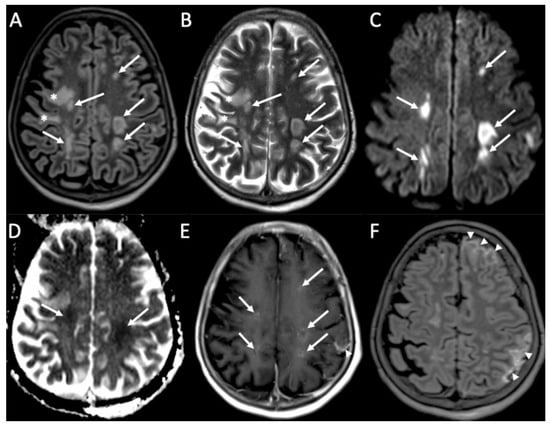

| Herpes Virus type 1 | • Mesio-temporal involvement • Bilateral and asymmetric pattern • Cortical hyperintensity on T2 and FLAIR, with restricted diffusion (acute phase) and cortical enhancement (subacute phase) • Hemorrhagic foci |

| Varicella Zoster Virus | • Leptomeningeal enhancement • Cerebellitis |

| Cytomegalovirus | • Hyperintense areas in T2 and FLAIR in the periventricular white matter • Ventriculitis |

| Human herpesvirus type 6 | • Similar to herpes virus type 1, but cortical enhancement is more common |